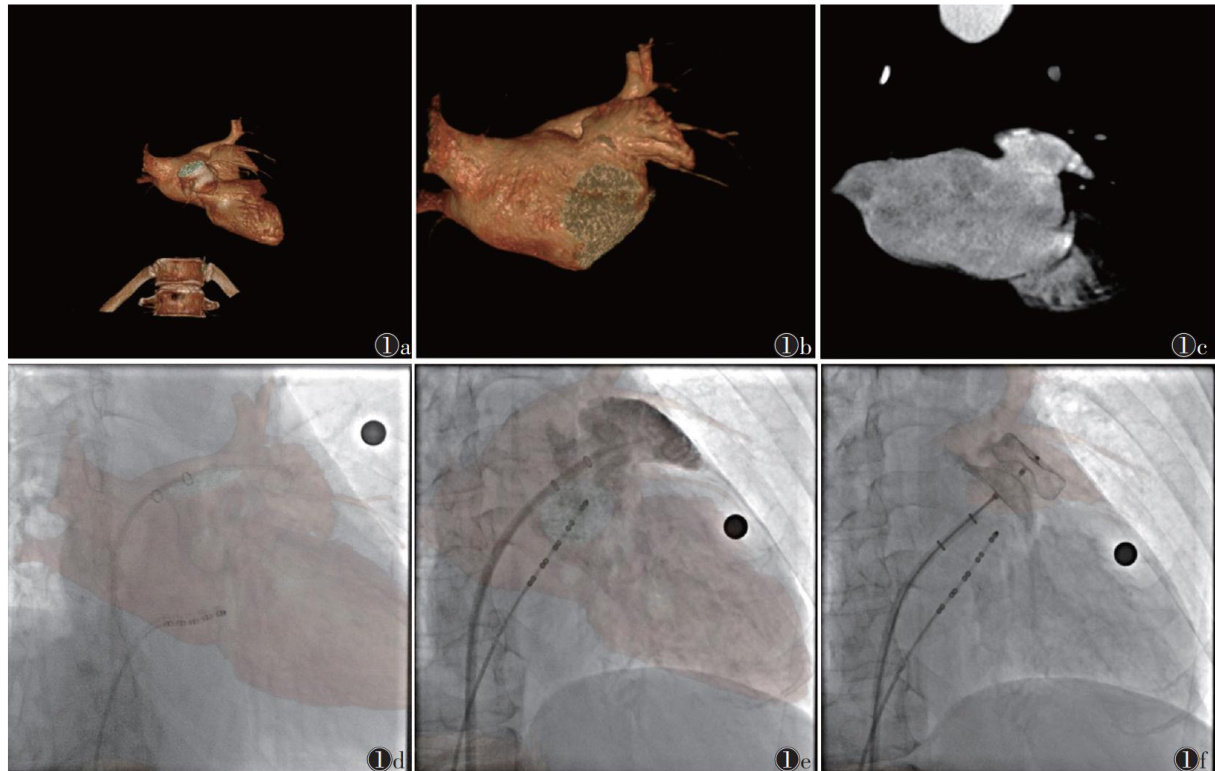

[摘要]目的:应用E-cervix宫颈弹性成像技术探讨正常妊娠孕妇不同孕期宫颈弹性参数的变化规律。方法:选取常规产检孕妇185例行E-cervix宫颈弹性成像,随访排除早产8例、胎儿严重畸形3例,最终纳入174例,其中妊娠12周49例妊娠,16周24例,20周24例,24周21例,28周21例,32周18例,36周17例。记录174例的弹性对比度指数(ECI)硬度比(HR)宫颈内口应变平均值(IOS)、宫颈外口应变平均值(EOS)、宫颈内外口应变比值(IOS/EOS)等宫颈弹性参数,分析宫颈弹性参数与孕周的关系并建立回归方程。结果:随孕周增加,HR呈降低趋势,ECI、IOS、EOS、IOS/EOS均呈升高趋势(均 P<0.05 )。HR与孕周呈负相关( r=-0.175 P=0.021 ),其线性回归方程为: HR=77.409-0.234× 孕周;ECI、IOS、EOS均与孕周呈正相关 (r=0.433,0.452 0.291;均 P=0.001 ),其线性回归方程分别为:

孕周, IOS=0.160+0.004× 孕周, EOS=0.204+0.003× 孕周。结论:随妊娠进展,正常妊娠孕妇宫颈的不均质性不断增加,宫颈硬度不断降低,且以宫颈内口的硬度降低为著。